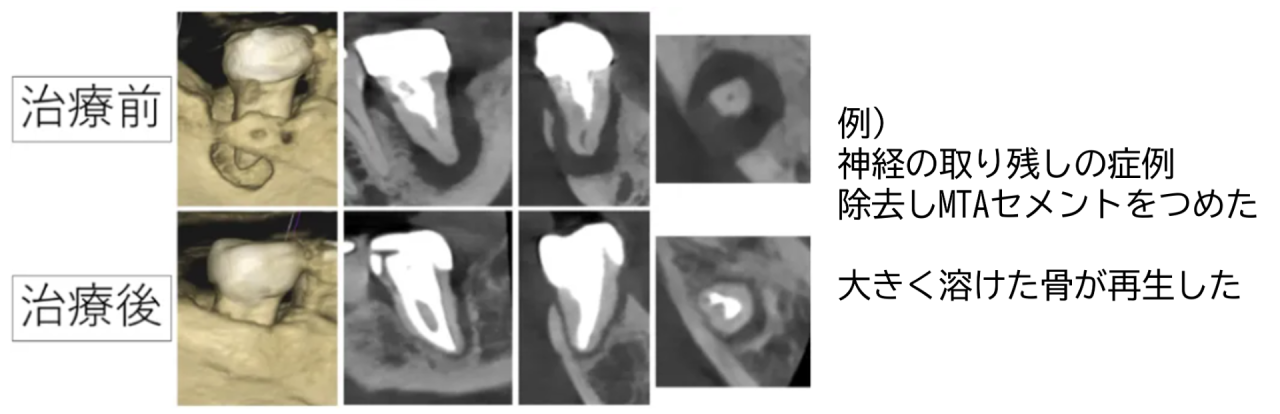

例えば神経の取り残しがあった時、取り残された神経の入り口を見つけることができます。

薬は根の中をしっかりと密閉することと、半永久的に長く殺菌作用があるものでないといけません。それらを満たすものとしては、MTAセメントが最も優れています。

当院では最新のバイオセラミック系のMTAセメントを使用することで、殺菌作用と病気で溶けてしまった骨の再生が起こるようにしています。